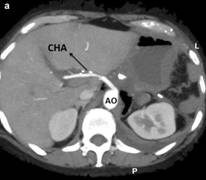

Ultrasonography of the abdomen revealed a hypoechoic 30x40 mm mass in the pancreatic body. Abdominal CT scan confirmed a solid heterogeneous mass of the pancreatic body, without cystic component. No radiologic signs of metastasis were found (Figure 1). Vascular reconstruction of CT scan showed a suspicious infiltration of the common hepatic and the splenic arteries with a total occlusion of the celiac trunk with a normal flow thought the gastro-duodenal artery. Furthermore, multiples atheromatous plaques with calcification were seen in the aorta. Similar findings were found in the pancreatic magnetic resonance. In the endosonographic study, the mass presents a high vascularization, confirming the infiltration of the major arteries at the origin of the celiac trunk. In the same study a biopsy was performed, compatible with adenocarcinoma.

Figure 1. Preoperative CT scan. a. A 4 cm tumor in the body of the pancreas narrowing of the vessels at the origin of the celiac axis due to tumor encasement. b. Superior mesenteric artery is not involved. CA: celiac axis; CHA: common hepatic artery; SA: splenic artery; SMA: superior mesenteric artery |